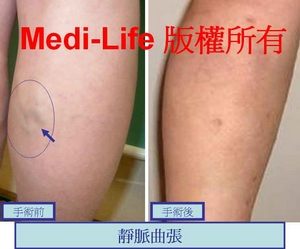

在進行全腿雕塑或蘿蔔腿手術的時候, 可以利用 TIPP (transilluminated powered phlebectomy, 經皮透視性、動力輔助式顯微手術) 或 顯微靜脈切除 特殊器械, 將青筋浮現的靜脈問題一併解決. 不用分好幾次療程-- [一次解決方案], 不會有另外的恢復期, 等於同時解決多項問題!! 更神奇的是恢復期不會加長, 而是同樣的時間處理掉多重問題.

許多女生都有這類靜脈浮現的問題, 雖然不至於到"曲張", 但是也妨礙觀瞻 !! 這也是可以解決的.

許多女生都有這類靜脈浮現的問題, 雖然不至於到"曲張", 但是也妨礙觀瞻 !! 這也是可以解決的.

另一個案例: 手術後三週照片

另一個案例: 手術後三週照片